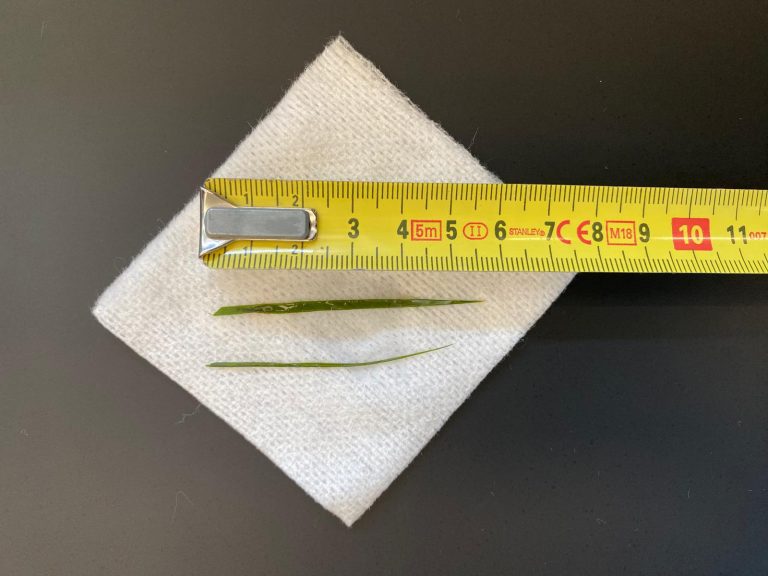

Ter controle, of de structuur nog in de buik aanwezig is, worden opnieuw röntgenfoto’s gemaakt. Hierop is het voorwerp nog goed zichtbaar, met een soort oogje erin. Het moet dus een naald zijn. De foto’s suggereren verder dat de naald niet in het maag-darmstelsel zit, maar in de buikholte.

Een paar dagen later is het zo ver. We maken voor de zekerheid opnieuw foto’s, om de juiste lokatie te controleren. De naald lijkt aardig op dezelfde plek te liggen.

Na het openen van de buik en het verwijderen van wat vet, is de chirurg gaan zoeken. Al snel vindt hij aan de voorzijde van de maag een vreemd vliesje. Dit blijkt een stukje vet en vlies te zijn, wat op het oogje van de naald verkleefd zat. Ruim 2/3 van de naald blijkt in een leverlob te zitten. De naald blijkt er niet eenvoudig uitgetrokken te kunnen worden. Hij zit aardig vast. Dit suggereert dat hij er misschien al iets langer zit. Bij het verwijderen van de naald ontstaat er een klein scheurtje in de lever. De bloeding kan worden gestelpt met een speciaal matje dat stolling bevordert. Hierna is het een kwestie van de buik sluiten en Lady mag weer wakker worden.

We zullen nooit helemaal zeker weten hoe de naald in de buikholte terecht is gekomen. Gezien de localisatie, de richting, het zwart zijn en het ontbreken van uitgebreide ontsteking er omheen is de gedachte dat hij in de maag gezeten heeft. Hier is hij door het maagzuur zwart geworden en steriel geworden. Waarschijnlijk is hij daarna door een maagbeweging door de wand heen gestoken. Lady heeft wat dat betreft veel geluk gehad; zou de naald de galblaas geraakt hebben of een groot bloedvat, dan was het anders afgelopen.